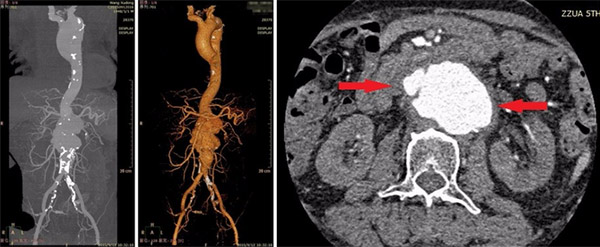

入院后,血管外科专家王兵副院长、崔文军副主任及值班医师王颖主治医师均高度重视,当天即急诊行胸腹主动脉联合CTA检查,出人意料的是腹主动脉瘤已经破裂!不幸中的万幸,破口位于腹膜后,出血刺激周围组织包裹,进而形成了假性动脉瘤,但即便如此,患者病情也异常凶险,随时有再次破裂出血风险,为挽救患者生命,手术治疗刻不容缓!

单纯肾下型的腹主动脉瘤目前多行覆膜支架腔内治疗,但该患者由于腹主动脉瘤瘤体较大,且已破裂,导致病变血管已累及到双侧肾动脉、肠系膜上动脉和腹腔干动脉,如此复杂的病变,临床上极为罕见,手术难度极大。如果选择腔内治疗,一旦置入覆膜支架,覆盖上述动脉,必将导致相应脏器的缺血坏死,后果不堪设想;如果选择开窗支架,单不说需要提前预定,几十万的费用都不是一般家庭所能承受的,最终我们选择传统的开放手术,行人工血管置换。但祸不单行,患者巨大的动脉瘤已压迫右侧肾动脉,导致肾脏萎缩,并出现了急性肾功能衰竭,入院时每日的尿量不足500ml,血肌酐高达596umol/l,且呈逐渐上升趋势,全身出现浮肿;入院前长期的高血压病史(200/100mmHg),导致患者心功能严重受损,左心室明显扩大,心脏储备功能差,患者如此的身体状况去做开放手术,手术风险巨大!

术前